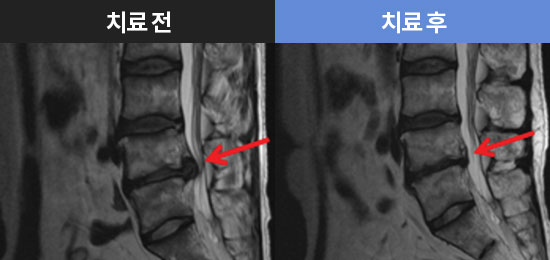

MRI로 보는 치료결과

참잘함한방병원의 MRI 치료 결과를 확인해 보세요.

수술 권유 받았던 허리 디스크! 입원 집중치료로 극복!

조회수35 2025.08.01